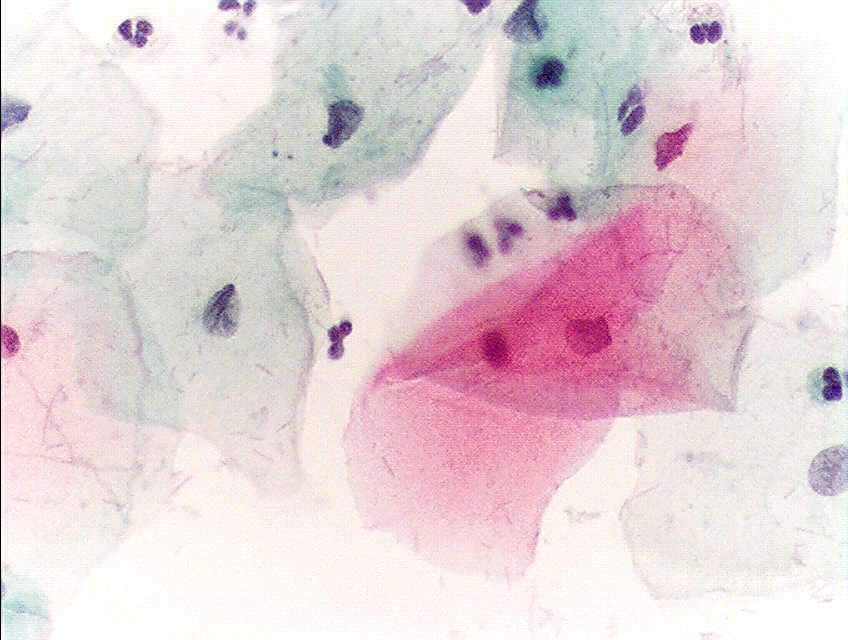

Σήμερα το τεστ Παπανικολάου (Τεστ-Παπ) χρησιμοποιείται παγκοσμίως για την διάγνωση του καρκίνου του τραχήλου της μήτρας, επί της προκαρκινικής δυσπλασίας και άλλων κυτταρολογικών ασθενειών του γυναικείου αναπαραγωγικού συστήματος.

Το 1923 εφάρμοσε τη μέθοδό του σε γυναίκες, προς μελέτη των φυσιολογικών γεννητικών λειτουργιών και στη συνέχεια για τη διάγνωση του καρκίνου του τραχήλου της μήτρας. Η πρώτη του ανακοίνωση επί της χρησιμοποίησης της κυτταρολογικής μεθόδου προς διάγνωση του καρκίνου του τραχήλου της μήτρας, το 1928, έγινε δεκτή με πολύ σκεπτικισμό, καθόσον η κρατούσα τότε γνώμη, για τέτοιου είδους έρευνα και εφαρμογή, επί αποφολιδουμένων κυττάρων ήταν πρακτικά αδύνατη. Τέτοια διάγνωση θεωρούνταν δυνατή, μέχρι την εποχή εκείνη, μόνο με την τομή του πάσχοντος οργάνου.

Οι έρευνες του Παπανικολάου επεκτάθηκαν στη συνέχεια στις κυτταρολογικές αλλοιώσεις στο καρκίνο του αυχένα της μήτρας και του ενδομητρίου, των οποίων τα πορίσματα δημοσίευσε το 1943 από κοινού μετά του καθηγητή γυναικολογίας Έρμπερτ Τράουστ σε ειδική μονογραφία υπό τον τίτλο «Διάγνωσις του καρκίνου της μήτρας μέσω των κολπικών επιχρισμάτων» (Diagnosis of Uterine Cancer by the Vaginal Smear).

Ο Παπανικολάου με τις εργασίες του αυτές έγινε ο θεμελιωτής νέου επιστημονικού κλάδου της «αποφολιδωτικής κυτταρολογίας» βασιζόμενη ακριβώς στη μελέτη των αποφιλιδουμένων κυττάρων του οργανισμού στις διάφορες κοιλότητες αυτού.

Η μέθοδος αυτή που έλαβε προς τιμή του την ονομασία «Μέθοδος Παπανικολάου» ή «Τεστ Παπανικολάου» και κατά συγκοπή «Τεστ Παπ» άνοιξε ευρείς νέους ορίζοντες στην ιατρική έρευνα στη γενετήσια φυσιολογία και ενδοκρινολογία ειδικότερα για τον καρκίνο.